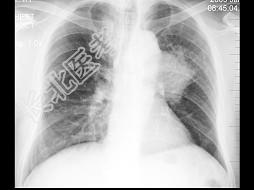

- 单项选择题男,57岁, 胸痛数月,近2天痰中带血, X线检查如图,最可能的诊断是 ( )

A、左肺不张

B、左肺炎症

C、左肺肿块

D、左肺门淋巴结肿大

E、正常心、肺、膈